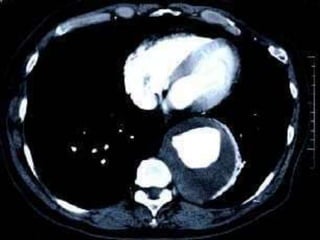

Hematoma retroperitoneal por ruptura de aneurisma de la aortaSurg Clin N Am 91 (2011) 185–193

Hematoma retroperitoneal porruptura de aneurisma de la aortaSurg Clin N Am 91 (2011) 185–193

TAC abdominalMuy sensible y específico, particularmente cuando se combinan medio de contraste, cortes finos y reconstrucciones tridimensionales con mediciones perpendiculares a la línea media de la aortaDa información precisa sobre la forma y relaciones anatómicas de los vasos renales, iliacos  y viscerales, así como la presencia de trombos murales, calcificaciones y ateroesclerosis oclusiva Se recomienda en caso de que se plantee tratamiento de reconstrucción aórticaSurg Clin N Am 91 (2011) 185–193

TAC abdominalPuede dar información errónea en el caso de aorta tortuosa, igual que la ecografíaInvasivo, pues requiere contrastes intravenosos y el uso de radiaciones ionizantesEs mas caro y de menor disponibilidad por lo que no se recomienda como técnica de screening inicialSurg Clin N Am 91 (2011) 185–193

TAC abdominalMuy sensibley específico, particularmente cuando se combinan medio de contraste, cortes finos y reconstrucciones tridimensionales con mediciones perpendiculares a la línea media de la aortaDa información precisa sobre la forma y relaciones anatómicas de los vasos renales, iliacos y viscerales, así como la presencia de trombos murales, calcificaciones y ateroesclerosis oclusiva Se recomienda en caso de que se plantee tratamiento de reconstrucción aórticaSurg Clin N Am 91 (2011) 185–193

TAC abdominalPuede darinformación errónea en el caso de aorta tortuosa, igual que la ecografíaInvasivo, pues requiere contrastes intravenosos y el uso de radiaciones ionizantesEs mas caro y de menor disponibilidad por lo que no se recomienda como técnica de screening inicialSurg Clin N Am 91 (2011) 185–193